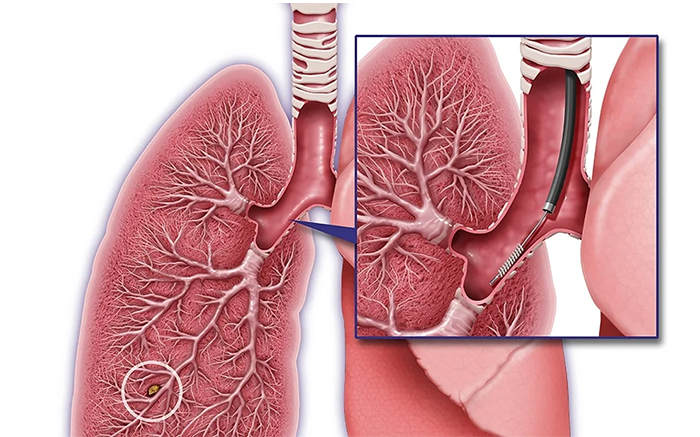

Specialist in Tuberculosis, Asthma, COPD, ILD, Pneumonia, Allergy, Bronchoscopy, Chest Diseases, Critical Care, and Sleep Disorders.